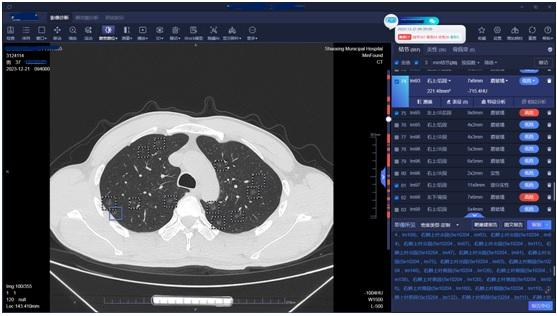

37岁的胡军(化名)最近做了个胸部CT,检查结果显示,其双肺长了557个磨玻璃结节,最大的直径1.2厘米。

(肺结节人工智能筛查影像)

“我从医快20年了,甄别过许多肺结节,这次遇到的病例非常特殊。”绍兴文理学院附属医院放射科副主任姚克林说,这些结节均大于3毫米,随机分布,密密麻麻。

胡军告诉医生,他3年前就查出多发性肺部结节,这几天出现咳痰、胸闷等症状。肺结节人工智能软件提示,其双肺竟有557个磨玻璃结节,其中高危的有26个。